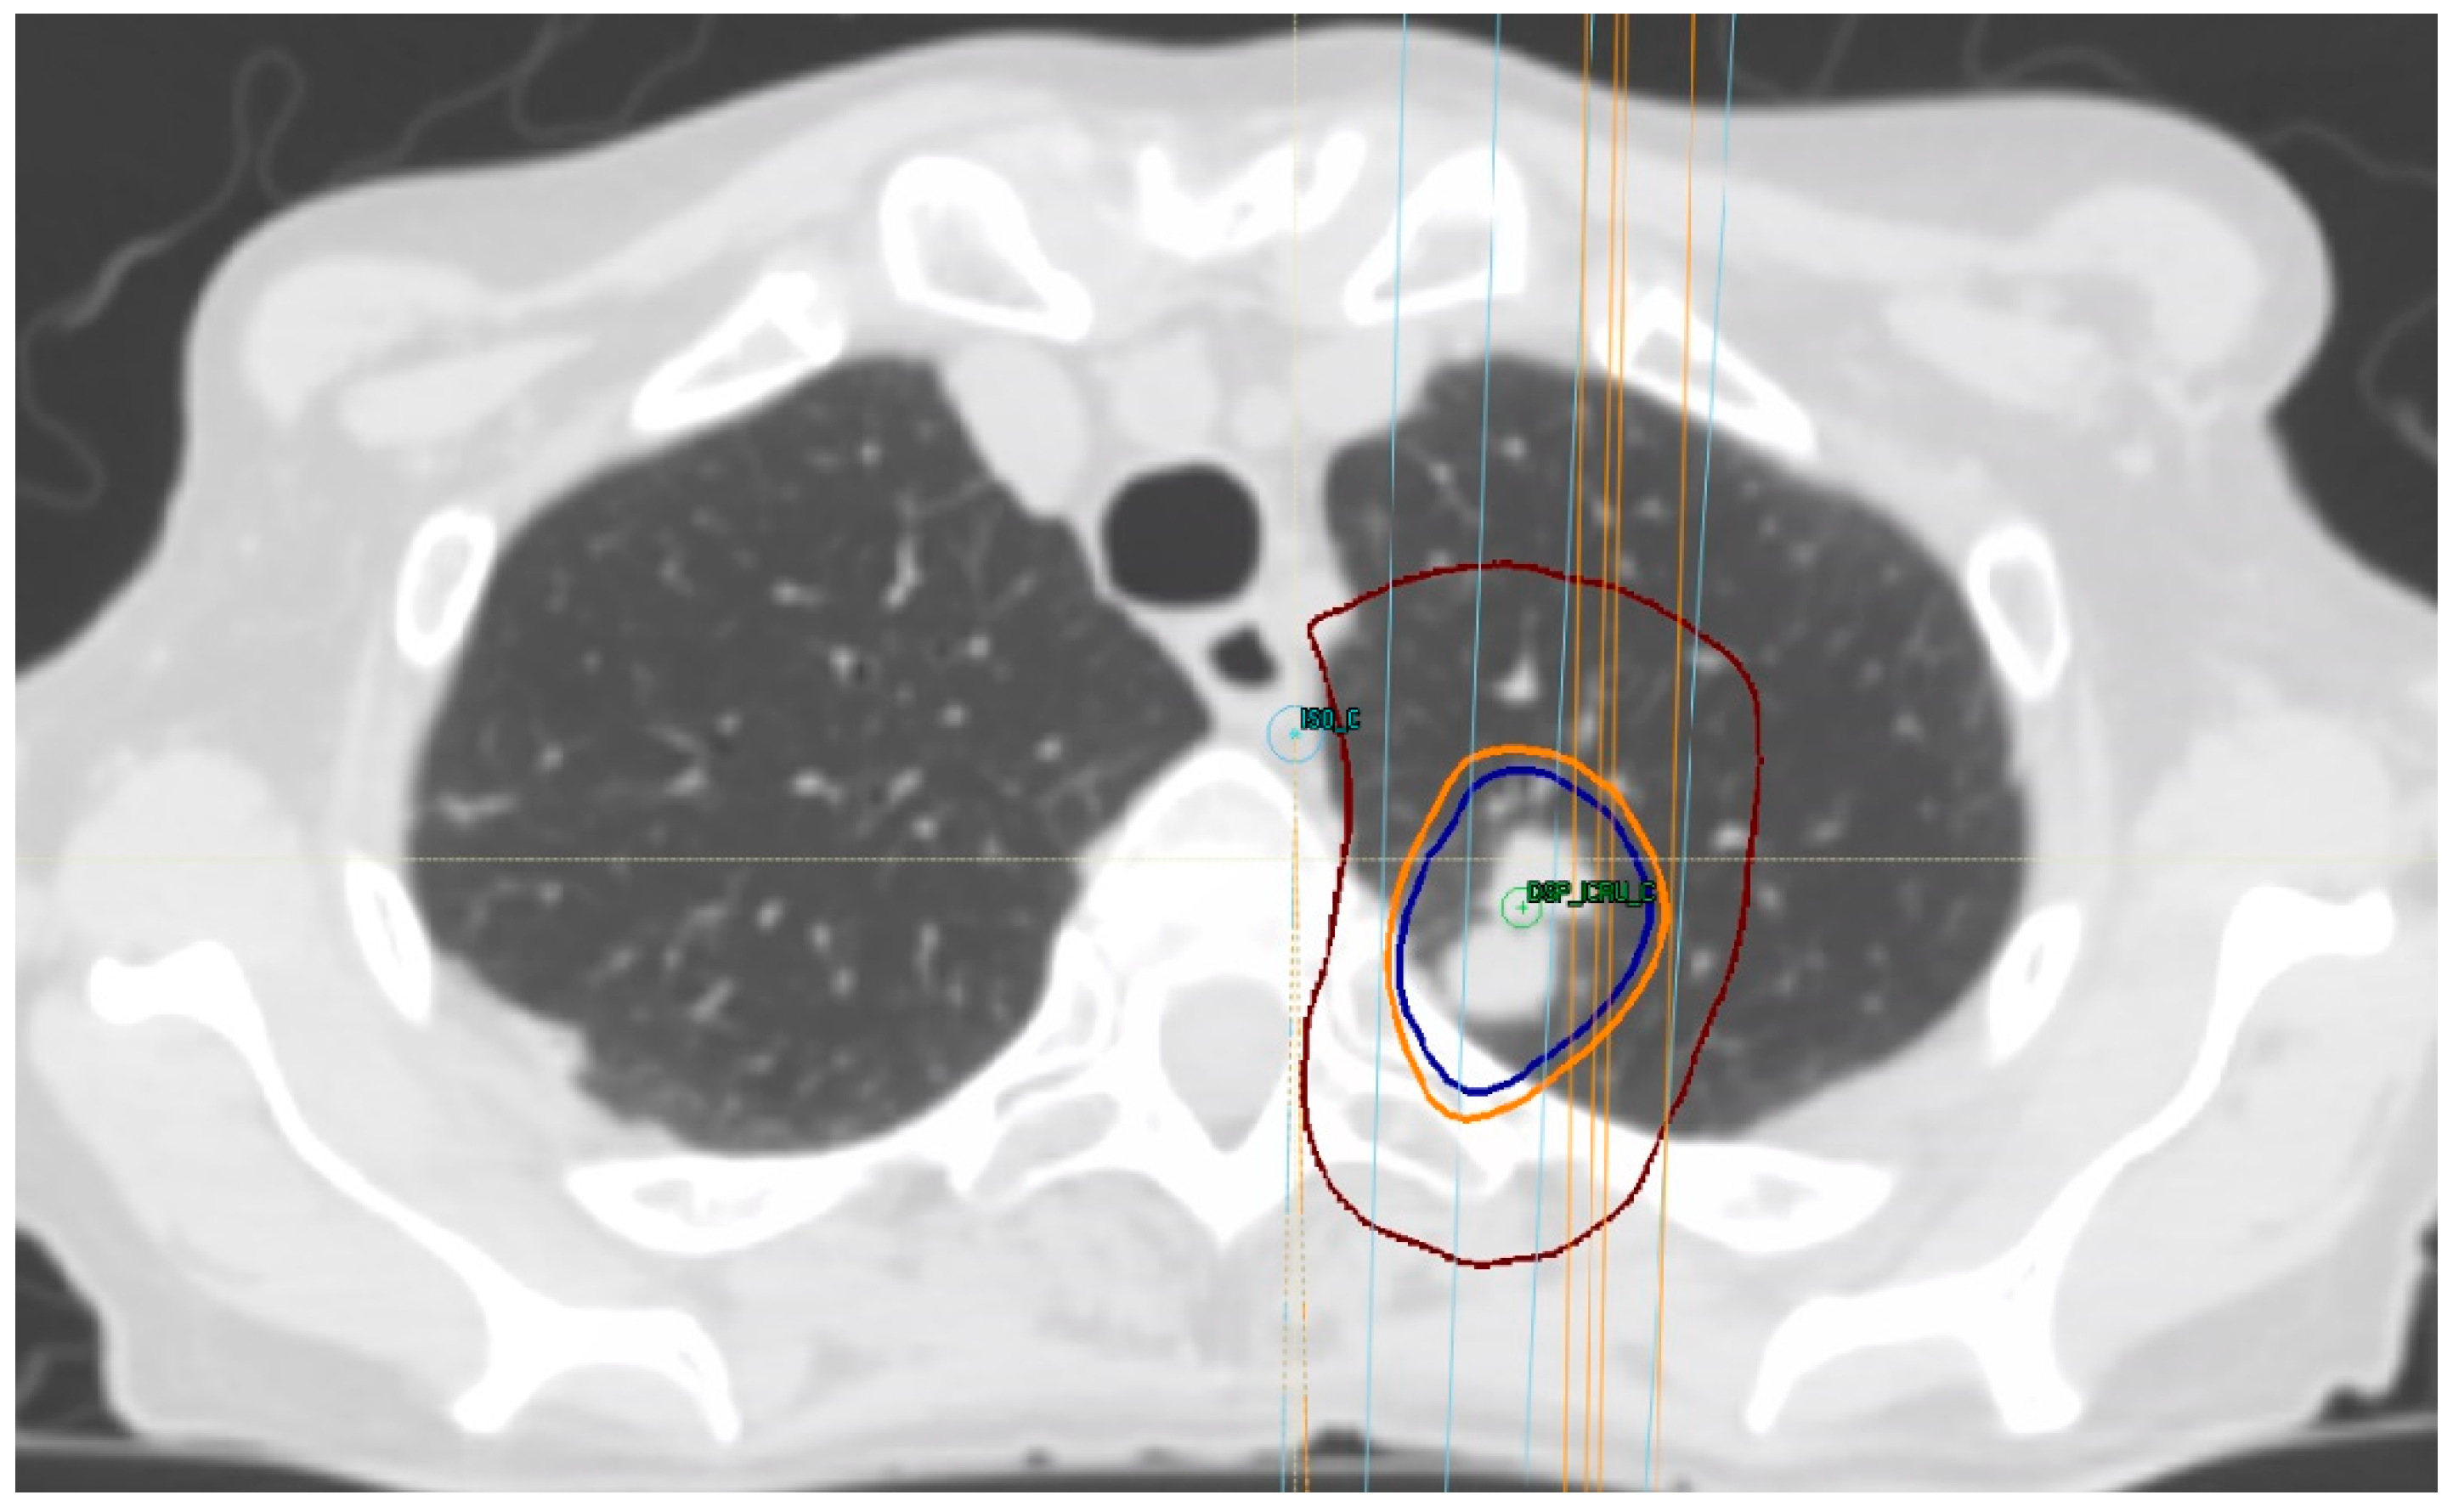

Traditionally, only patients with tumors at least 2 cm away from the bronchial tree have been considered for SBRT, following a commonly used three to four fraction regimen [15] (Figure 2). However, at present, patients with central tumors, defined as those where the closest point is within 2 cm proximal to (but not contacting or abutting) the main bronchial tree or within 2 cm (contacting or not) of mediastinal structures [74,75], are at higher risk for toxicity when treated with SBRT, compared to patients with peripheral tumors [34], avoiding the use of a three-fraction regimen is recommended in this scenario [42]. Tumors with the highest risk for SBRT are those with an ultra-central location, defined as any GTV at ≤1 cm from the proximal bronchial tree that overlaps the trachea or the main bronchus [75] or tumors that contact (abut) the proximal bronchial tree [74,75]. High rates of toxicity and death are associated with treatment in this situation, increasing the interest in identifying an optimal, effective, and safe dose for this group of patients [76].

Figure 2.

Treatment-planning dose for lung SBRT in a patient with biopsy-proven metastatic breast cancer, prescribing 48 Gy in four fractions. Isodose lines: Burgundy, 24 Gy; light orange, 44 Gy; and blue, 48 Gy.